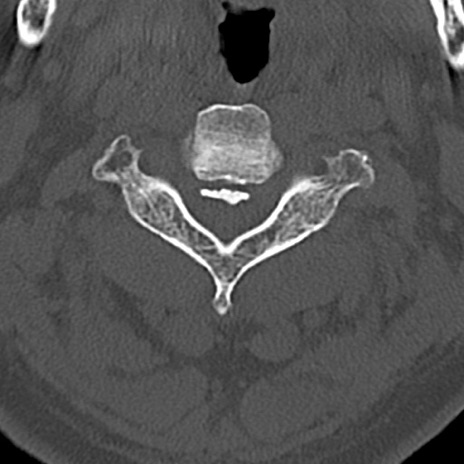

頚椎CT

横断像